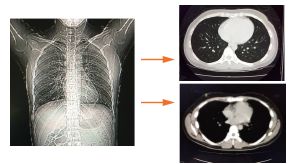

当院ではCANONメディカルシステムズ社の「Aquilion CX」を使用しております。

CT検査は数十から数百枚の体を輪切りにした画像を作成して医師が診断を行います。レントゲンに比べて病気の発見率があがります。

胸部CT

通常の胸部レントゲンに比べて

断面像のため心臓や肋骨に隠れた小さな早期病変を発見できます。肺がんだけでなく、肺気腫や心臓、血管に起こる様々な病気の早期発見が可能です。